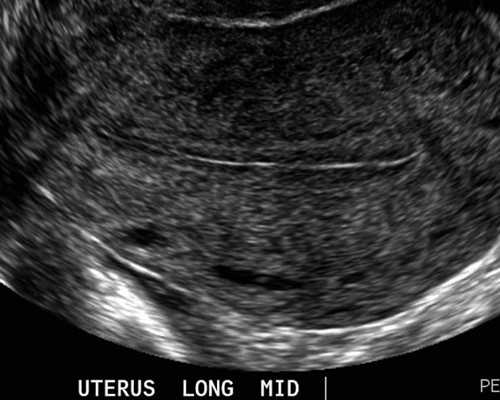

一般来说,我们做一次试管婴儿的总共费用,大概在3万-5万左右。做试管婴儿建议月经来潮的第10天到医院做彩超,以此来监测卵泡,待卵泡成熟之后再注射绒毛膜促性腺激素1万个单位来促排,等卵子排出来后再跟精子相结合,移植到女性的子宫内。要是患者们不排卵的话,平时要注意适当的进行调理,饮食方面要合理的搭配,增加饮食的营养之后再养成规律的作息,从而改善体质。

内膜5mm。